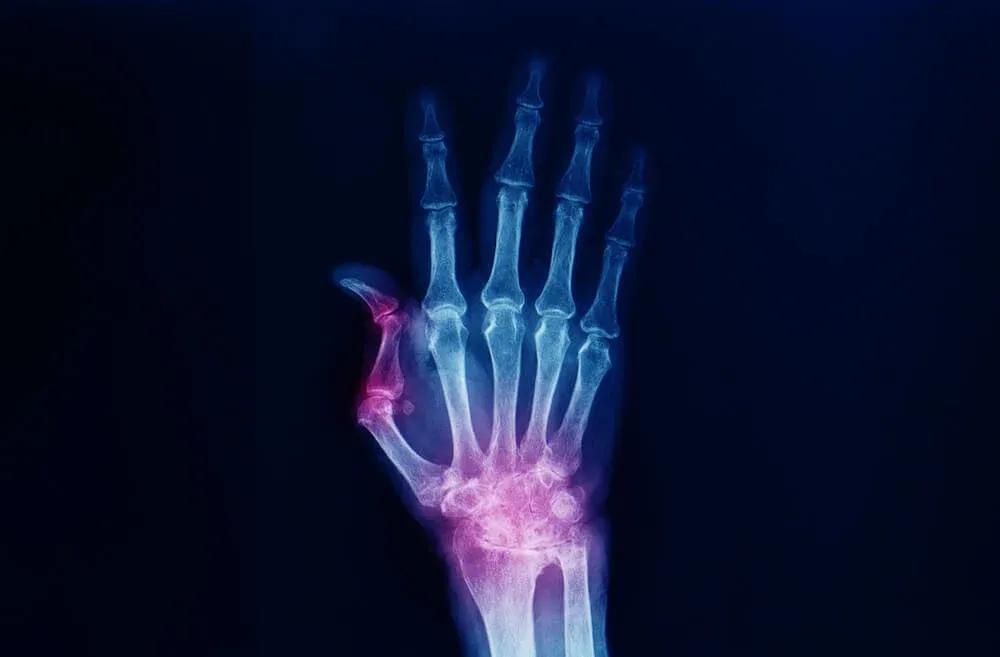

Bei Arthrose an der Daumenbasis ist der Knorpel zwischen den Knochen abgenutzt. Das führt zu Schmerzen beim Greifen, Drücken oder Drehen. Eine Bandage stabilisiert und verhindert übermäßige Bewegungen. So kommt das Gelenk zur Ruhe, was die Beschwerden lindert. Auf diese Weise kannst du deine täglichen Aufgaben weiterhin ausführen, jedoch mit mehr Unterstützung.